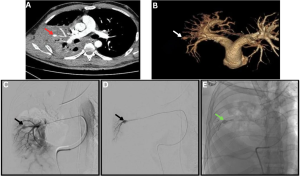

Fig 17: Clinical history:

A 35-year-old male with a history of severe COVID-19 presented to the emergency department with fever, breathlessness, and massive hemoptysis.

Figure A:

Axial CT pulmonary angiography (CTPA) image demonstrates cavitary consolidation in the right upper lobe with a pseudoaneurysm arising from the posterior segmental branch of the right pulmonary artery (red arrow).

Figure B:

Three-dimensional volume-rendered reconstruction highlights the pulmonary artery pseudoaneurysm (white arrow).

Figures C & D:

Selective pulmonary angiograms confirm a pseudoaneurysm arising from the posterior segmental branch supplying the right upper lobe (black arrows).

Figure E:

Post-glue embolization angiogram demonstrates complete occlusion of the pseudoaneurysm (green arrow).

Microbiology: Bronchoalveolar lavage culture and sputum microscopy confirmed pulmonary mucormycosis.